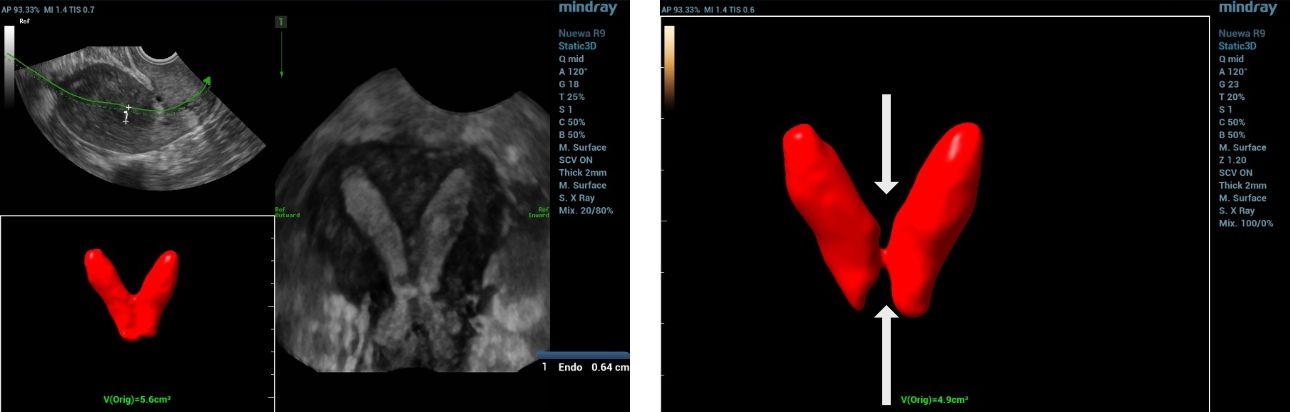

To further assess the anatomy, a 3D ultrasound was conducted, which provided the true coronal view of the uterus. This enabled better visualization of the uterine cavity and external contour, allowing for more accurate classification.

Based on the 3D ultrasound findings, the impression was complete septate uterus with septate cervix.

complete septate uterus and cervix

Furthermore, the application of Smart ERA (Endometrial Receptivity Analysis) enhanced the diagnostic evaluation by providing automated, high-resolution analysis that clearly delineated the septate uterus and septate cervix, thereby supporting the 3D ultrasound findings.

Three-dimensional ultrasonography is now the gold standard for evaluating uterine morphology, offering clear visualization of both the cavity and external contour [7]. In this case, 3D ultrasound accurately identified a complete septate uterus with septate cervix, a diagnosis that could be easily missed with 2D imaging.The addition of Smart ERA provided automated analysis and clearer delineation of the septal structure, enhancing diagnostic precision and reducing operator dependency. Early and accurate detection supports timely reproductive counseling and appropriate management [8].